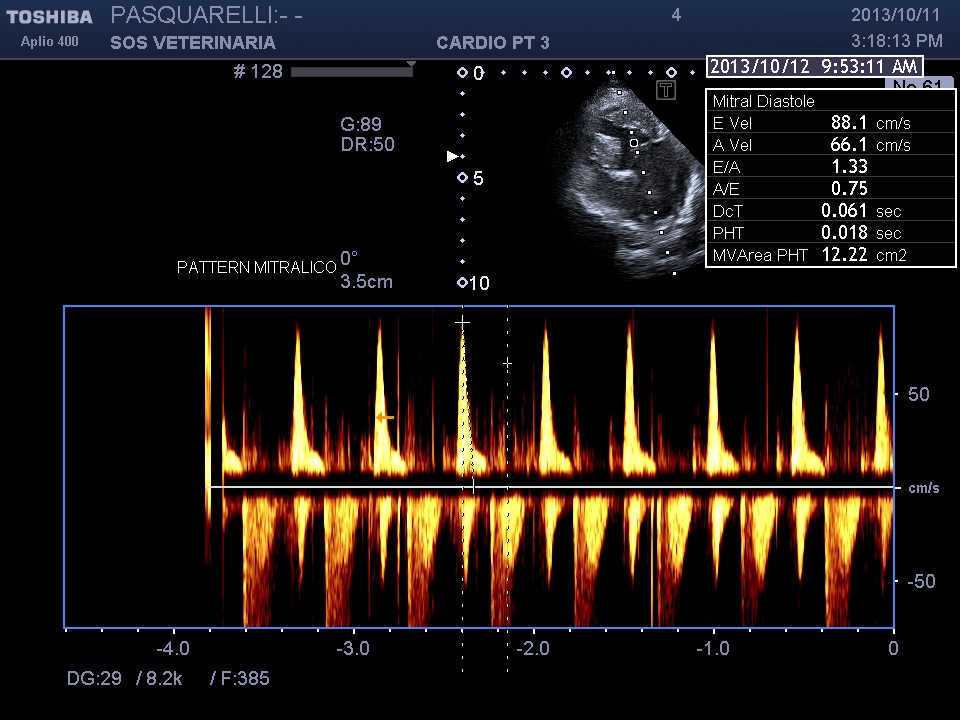

caso di cardiomiopatia ipertrofica del Maine Coone ,presentazione al pronto soccorso tipica con edema polmonare e tromboembolismo aortico completo bilaterale ,per la mia esperienza,nessun trattamento risulta essere efficace per questi soggetti, il decesso avviene nel 90%-95% dei casi e quelli che sopravvivono muoiono nelle settimane successive per le severe complicanze provocate dall’ipoperfusione ,i trattamenti trombolitici non risultano praticabili per diverse ragioni, non ultima quella economica, l’evento drammatico non e’ lo scompenso cardiaco diastolico (sul piano farmacologico gestibile) ma la trombosi aortica spesso anche polmonare .

Per avere una idea del grado di pericolosita’ della malattia basta visionare lo smoke (effetto fumo) nell’atrio sx del soggetto e il voluminoso trombo fluttuante e martellante i lembi valvolari .